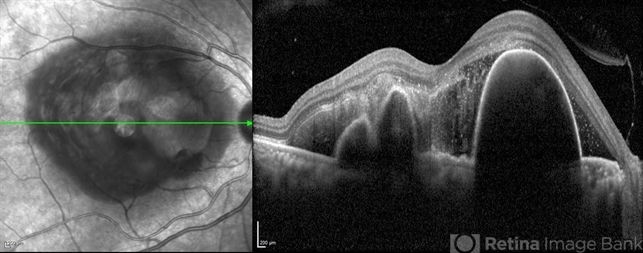

- Polypoidal choroidal vasculopathy

- polypoidal choroidal vasculopathy (PCV)

Optical coherence tomography system

Heidelberg Spectralis - Description

- SD-OCT of a 60 year old woman revealing a large PED , multilobular PED and subretinal hemorrhage .